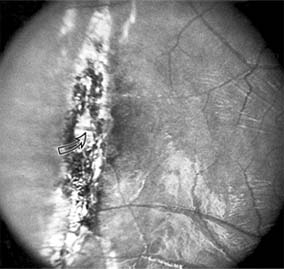

Central serous chorioretinopathy is characterized by serous detachment of the sensory retina as a consequence of focal leakage of fluid from the choriocapillaris through a defect in the retinal pigment epithelium (Figures 10-2 and 10-3). This disease typically affects young to middle-aged men and may be related to life stress events. Most patients present with the sudden onset of blurred vision, micropsia, metamorphopsia, and central scotoma. Visual acuity is often only moderately decreased and may be improved to near-normal with a small hyperopic correction.

Figure 10-2

Figure 10-2: Central serous chorioretinopathy with sensory retinal detachment (arrows) extending into the fovea.

Figure 10-3

Figure 10-3: Fluorescein angiogram of central serous chorioretinopathy shows active disease with both a retinal pigment epithelial detachment (small arrows) and a sensory retinal detachment (large arrows). Two foci of inactive disease (open arrows) are also present.